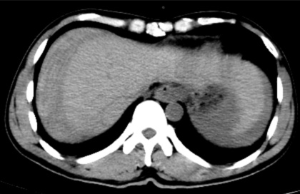

据悉,患者既往有多年乙型肝炎病史,突发右上腹剧烈疼痛入院。患者入院时血压70/40mmHg,心率110次/分,全腹压痛。血常规血红蛋白87g/L,甲胎蛋白>1210 ng/ml。腹部B超检查及CT平扫检查示“肝肿瘤并出血,腹腔积血积液”。